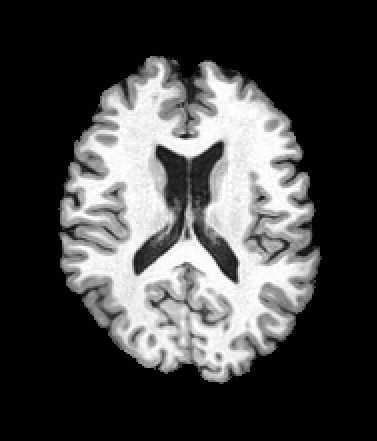

A trained MetaVoxel model can be unconditionally sampled by drawing Gaussian or categorical noise for each variable at timestep , and iteratively apply the denoising network until reaching . Unlike conventional diffusion models that focus solely on image generation, MetaVoxel can generate coherent synthetic patient profiles from the joint distribution , as shown in Figure 2.

| Age: 64.0 | Age: 53.8 | Age: 70.9 | Age: 76.9 |

| Sex: Male | Sex: Female | Sex: Female | Sex: Male |

![]() |

| Age: 80.9 | Age: 77.7 | Age: 73.2 | Age: 84.6 |

| Sex: Male | Sex: Female | Sex: Female | Sex: Female |